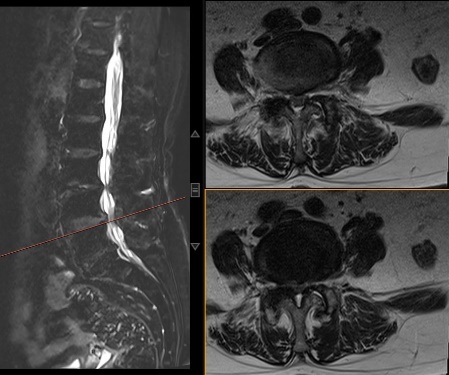

多年来,赵阿姨四处求医,但始终未能解决问题。直到三个月前,她经人介绍,找到我院骨科脊柱团队。蒋帅副主任经过详细问诊,判断她的症状属于“间歇性跛行”,是“腰椎管狭窄症”的典型表现。进一步的腰椎核磁共振(MRI)检查证实了这一诊断。

术前核磁图片